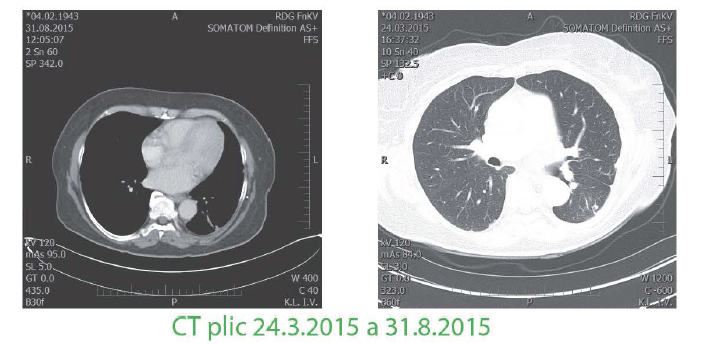

Poslední restaging

8/2015 bez známek diseminace či recidivy v oblasti odstraněných metastáz, pacientka ve výborném klinickém stavu bez neurologických či kognitivních poruch, bez dýchacích obtíží, zažívání prakticky bez komplikací ECOG 0-1